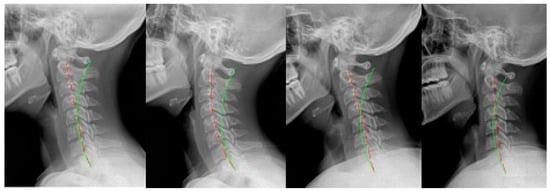

2.5. Case 5

2.6. Case 6

2.7. Case 7

3. Results